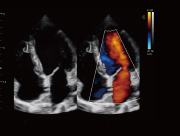

心脏,经食道